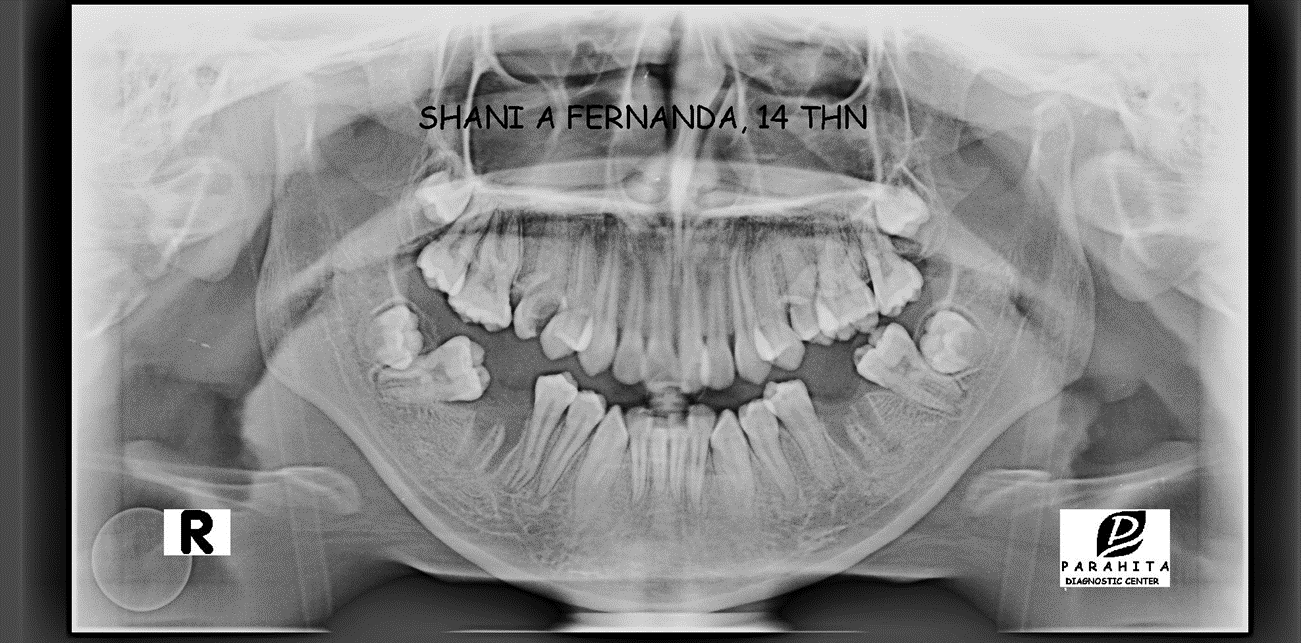

Figure 4. Foto Panoramic

Berdasarkan foto panoramic(gambar 4) ditemukan impaksi gigi pada 18 dan 28. Perhitunga sefalometri menunjukan skeletal kelas I dengan ANB 3º. Relasi gigi didapatkan bahwa inklinasi gigi rahang atas normal (I-NA 20º) dan gigi rahang bawah normal (I-NB 24º) dan terdapat rotasi mandibula ke bawah dan ke belakang (Gbr.3). Analisis jaringan lunak menunjukkan bahwa bibir atas dan bawah menonjol (Tabel 1). Berdasarkan dari anamnesa dan pemeriksaan klinis dimungkinkan bahwa etiologi maloklusifaktor herediter.